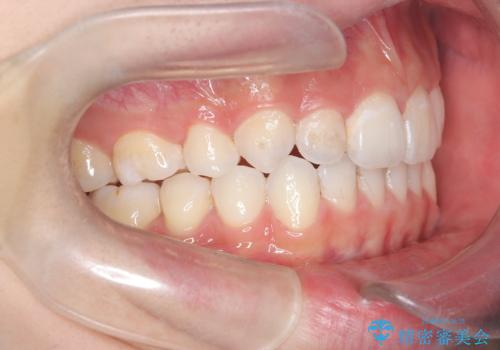

- 前歯が出ていることを主訴に来院されました。

臼歯関係が上顎前突傾向のため、上顎小臼歯を抜歯してインビザラインにて治療を行いました。